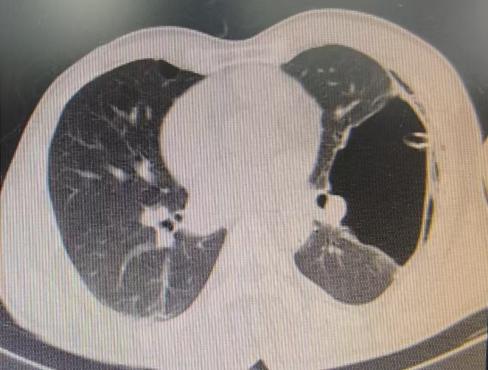

近期,国内知名呼吸介入专家陈愉教授联合做爱自拍 呼吸与危重症医学科团队,为李先生施行“胸腔镜下肺大疱探查术 + 胸腔闭式引流术”。手术中,陈愉教授运用单孔胸腔镜技术,仅在患者胸壁开了一个1cm的小切口。通过高清胸腔镜系统探查发现,患者胸腔内存在广泛粘连以及多发微小肺大疱,肺叶解剖结构异常,肺门血管直接暴露,经判断肺大疱腔已与胸腔贯通。

面对这一复杂状况,陈教授凭借丰富的经验果断调整手术方案。在确保安全的前提下,对可疑病灶进行了精准活检取样,随后精准置入胸腔引流管。术后即刻CT确认引流管位置良好,同时制定了严密的术后管理方案:每日监测引流量及肺复张情况,若引流量持续减少且肺大疱逐渐缩小,则按计划拨管;若肺大疱未明显缩小,则考虑拔除引流管后转外科进行胸膜剥离术。

术后复查CT显示,肺大疱明显缩小,患者胸闷症状显著减轻。整个手术过程进展顺利,患者术后恢复良好。

(术前左肺肺大疱明显-术后肺大疱逐渐缩小闭合)